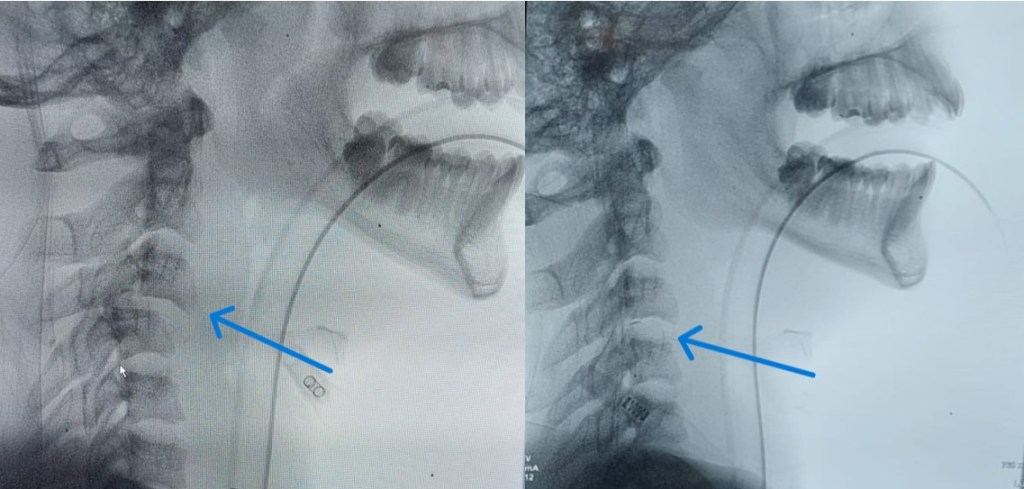

-Inestabilidad craneocervical: Viene definida por la presencia de una movilidad excesiva en la charnela craneocervical, esto es, la articulación entre el hueso occipital (C0) y el complejo atlo-axoideo (C1-C2 y sus correspondientes ligamentos). Esto puede originar una deformidad, que a veces precisa de estudios dinámicos para ser puesta de manifiesto, con o sin dolor y/o déficit neurológico. Entre sus causas se encuentran afectaciones congénitas (como el «os odontoidum«, la enfermedad de Morquio, el síndrome de Down, Arnold Chiari, etc), afectaciones infilamatorias (artritis reumatoide o espondilitis anquilosante), traumáticas (fracturas), infecciosas (Síndrome de Grisel, típico en edad pediátrica) o tumorales (metástasis o tumores óseos primarios). Su tratamiento es generalmente quirúrgico a veces precedido de la reducción mecánica para corregir la deformidad.

En el centro y a la derecha se aprecia el TAC postoperatorio en el se ha llevado a cabo la reducción de la luxación con un adecuado alineamiento y fijación combinada anterior mediante caja intersomática y placa así como posterior con tornillos a masas laterales.